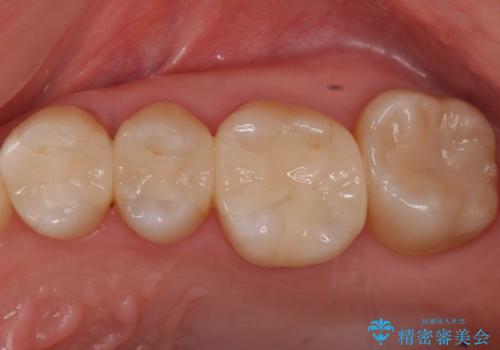

目立たない白いものがご希望とのことで、セラミックインレーで修復しました。

- 21万円(左上567:セラミックインレー 7万円x3本)費用は治療当時の料金となります

仮づめの状態でしたが、そこまで中は虫歯になっておらず、神経の治療も不要でした。